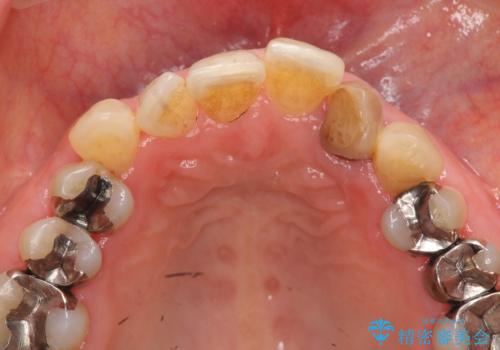

- 目立つ前歯の著しい変色の改善を求めて来院されました。

根管治療が為されたまま、クラウンの装着が行われず変色し審美障害を来している状態です。

維持を保つためのファイバーコア築盛を行い、精密なジルコニアクラウン製作を行います。